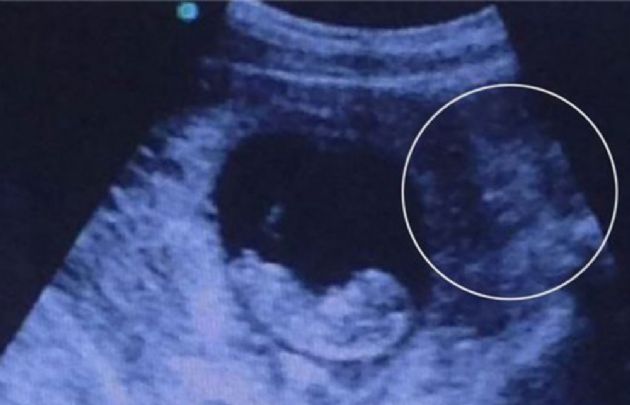

La imagen de un bebé en gestación se volvió viral después de que una persona la subiera a internet. A poco tiempo de ser compartida, más de medio millón de personas vieron la foto y surgieron las más variadas hipótesis.

La primera persona que vio “algo más” preguntó si era el único que veía al demonio en la parte derecha de la imagen, y recibió como respuesta que era una diosa hindú. Entre otras teorías, señalaron que la mancha que aparece es una “amigable sirena”.

La foto había sido posteada en el sitio imgur el primer día de este año, acompañada por la leyenda: “Ecografía de un amigo. Cuando ves esto...”.